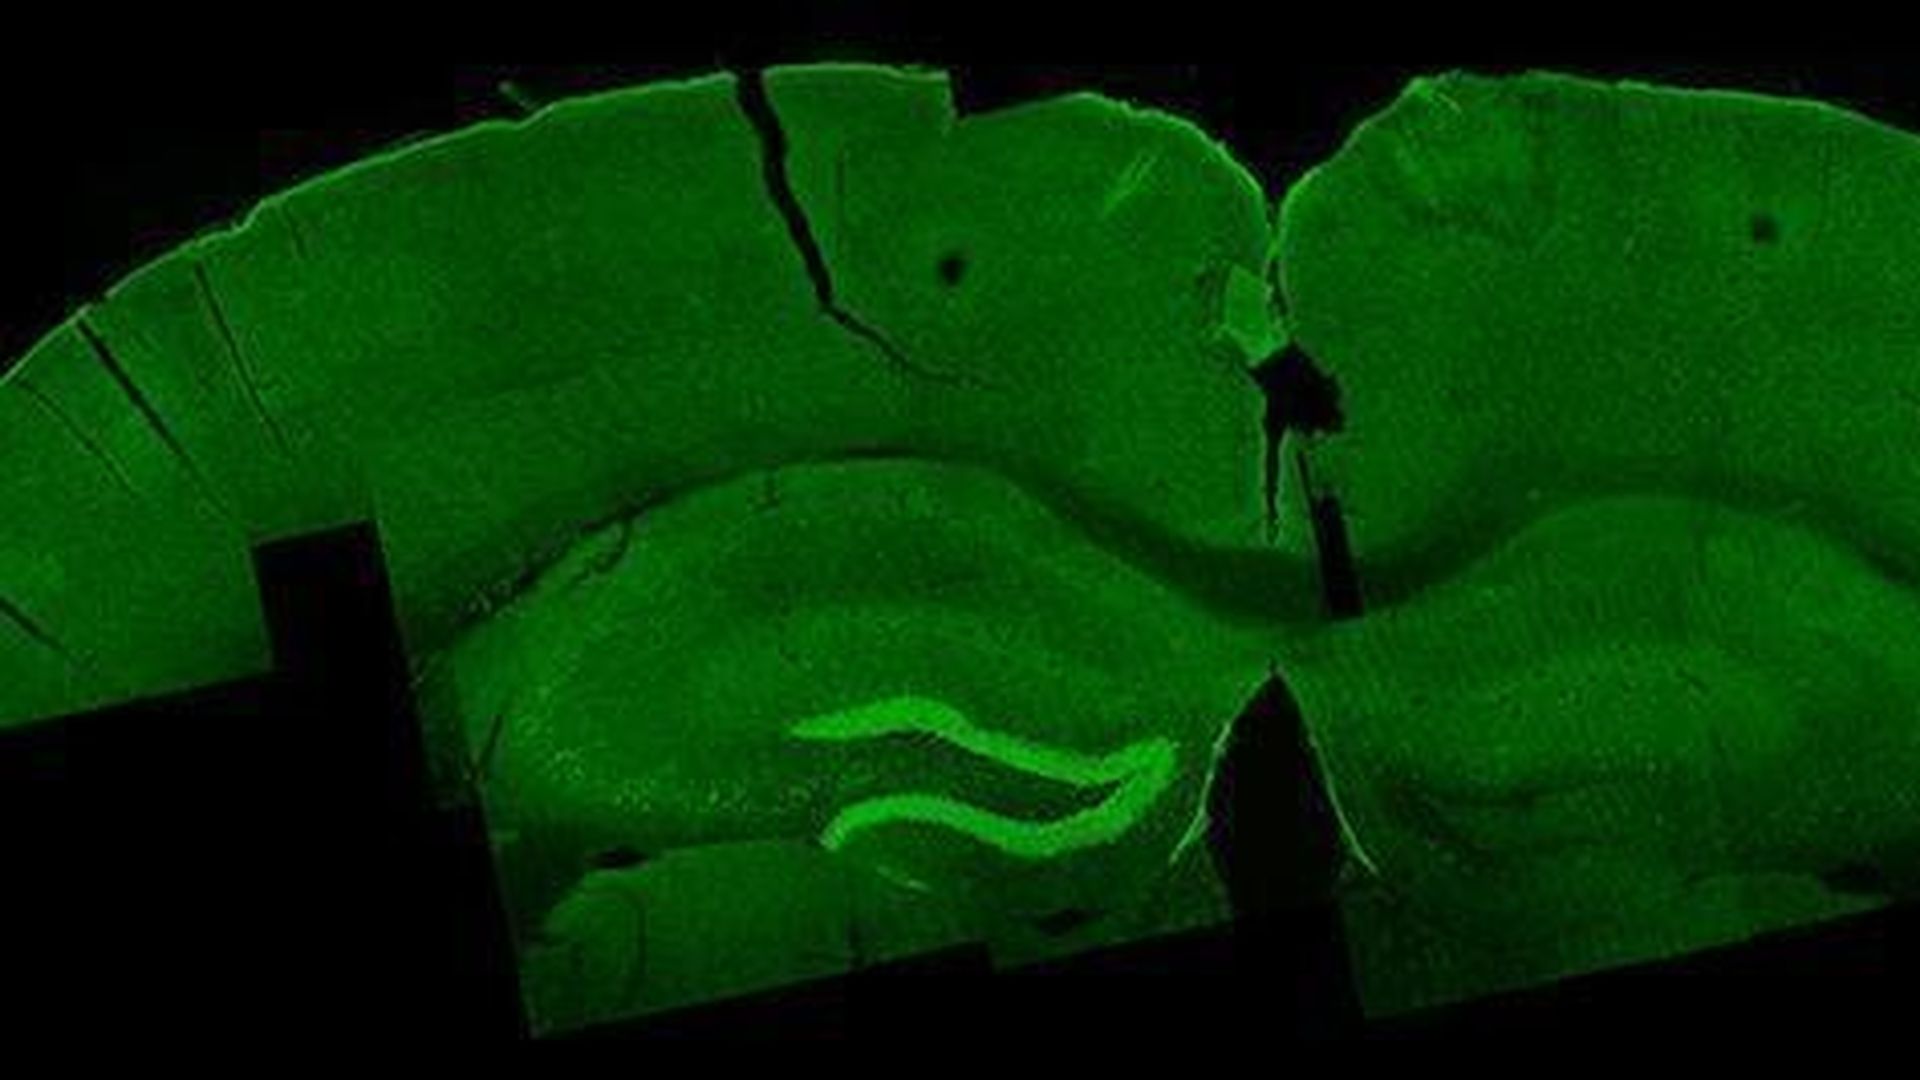

Researchers find new way to stimulate neurons deep in brain

Nir Grossman, Suhasa B. Kodandaramaiah and Andrii Rudenko.